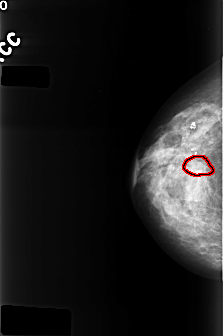

C_0394_1.RIGHT_MLO

FILE: C_0394_1.RIGHT_MLO.OVERLAY

TOTAL_ABNORMALITIES 1

ABNORMALITY 1

LESION_TYPE CALCIFICATION TYPE AMORPHOUS DISTRIBUTION CLUSTERED

ASSESSMENT 4

SUBTLETY 2

PATHOLOGY BENIGN

TOTAL_OUTLINES 1

BOUNDARY